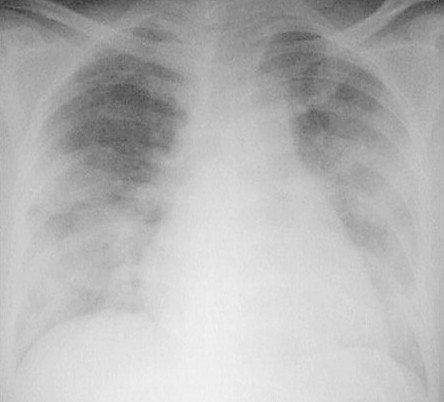

病例1:重症肺炎

男性,85岁,发热、气短。1月17号表现为两肺斑片状实变影,经过一轮治疗,效果欠佳,病情继续进展,两肺比较对称,没有心衰,也没有水肿的改变。最终诊断是重症肺炎,调整碳青霉烯类药物的治疗后有所好转。

c5ab476ddc622fb9cfc67f8a5cfda05b.jpg